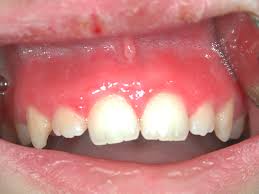

gingivitis

Definition: Inflammatory response resulting from the biofilm accumulation located below the gingival margin

gingival health: <10%, localized gingivitis: 10%-30%, and generalized gingivitis: >30%

JE at CEJ; 3mm or greater; reversible